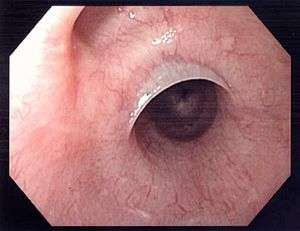

Esophageal webs are thin membranes located in the middle or upper esophagus.

Esophageal webs are thin (2-3mm) membranes of normal esophageal tissue consisting of mucosa and submucosa that can partially protrude/obstruct the esophagus. They can be congenital or acquired. Congenital webs commonly appear in the middle and inferior third of the esophagus, and they are more likely to be circumferential with a central or eccentric orifice. Acquired webs are much more common than congenital webs and typically appear in the cervical area (postcricoid).

Esophageal webs are more common in white individuals and in women (with a ratio 2:1). The literature describes relations between these webs and Plummer-Vinson Syndrome, bullous dermatologic disorders, inlet patch, graft-versus-host disease and celiac disease. The postulated mechanisms are sideropenic anemia (mechanism unknown) or some interference of the immune system. Esophageal webs can be ruptured during upper endoscopy.